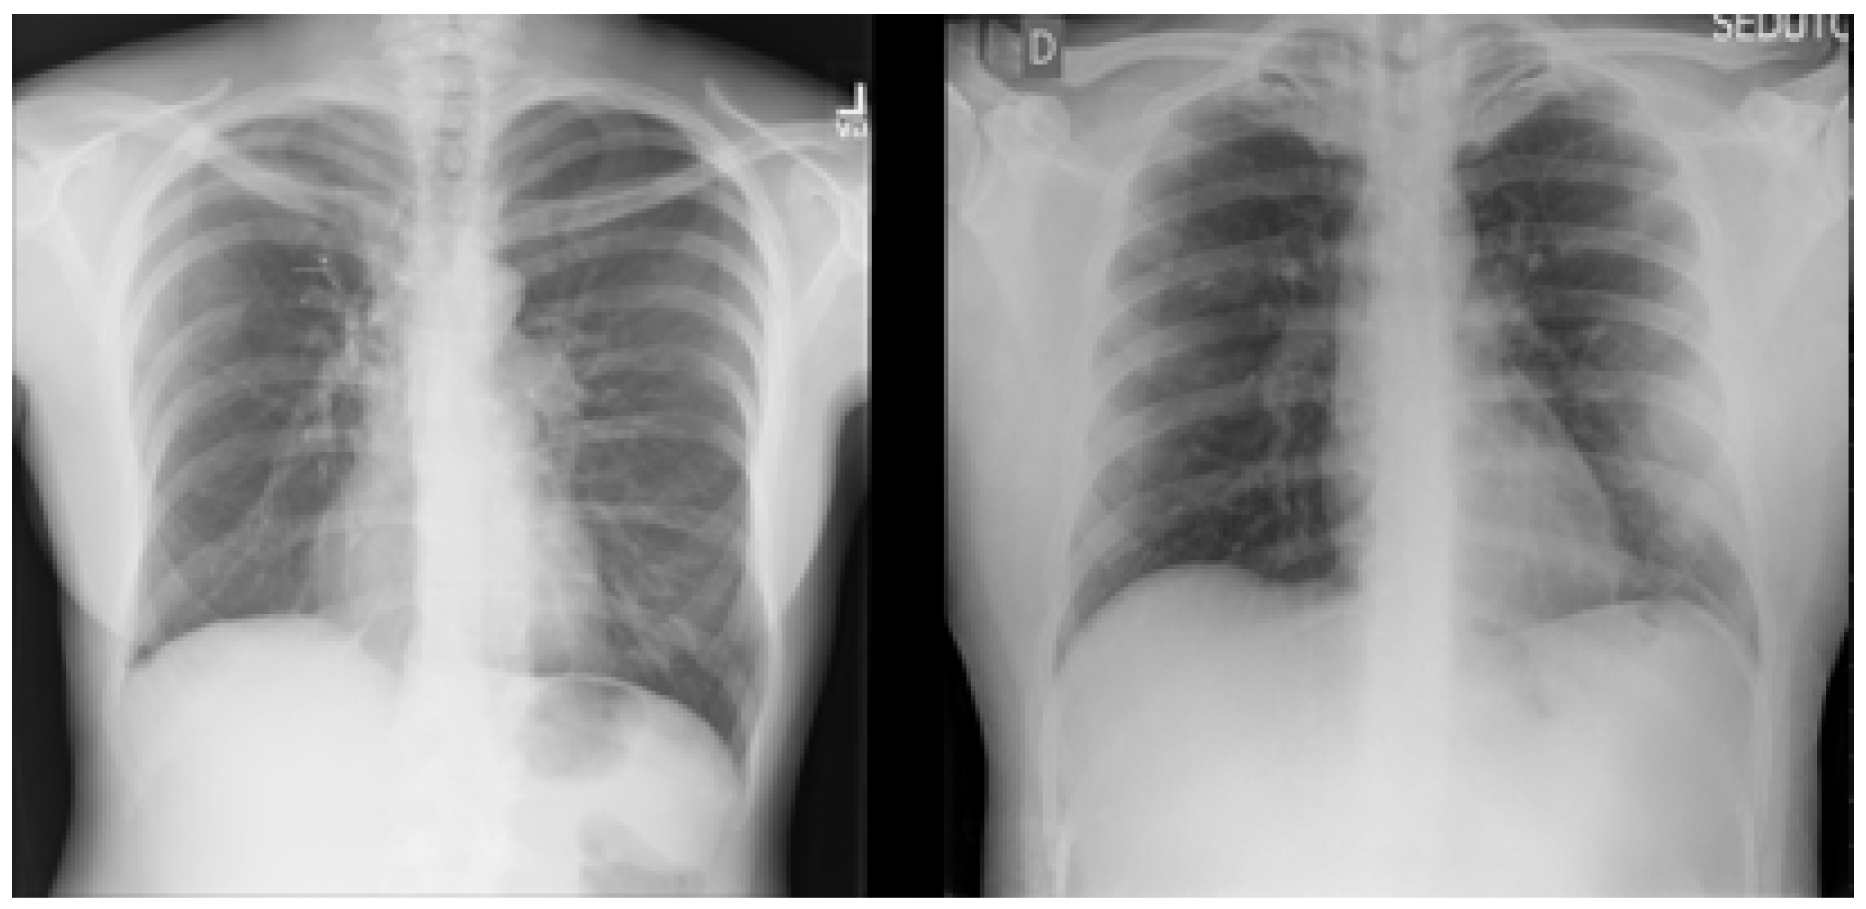

For the binary classification task used in this research, the dataset consisted of 15,000 X-ray images, labeled with two classes: (1) Normal (which meant that the patient was healthy and did not suffer from any pneumonia type); and (2) Abnormal (which meant that the patient was suffering from pneumonia because of Coronavirus or other types of viruses). Figure 3 shows an example of the dataset (X-ray images) classes used for the binary classification task: Normal and Abnormal, respectively, from left to right.

Figure 3. X-ray images of Normal and Abnormal.